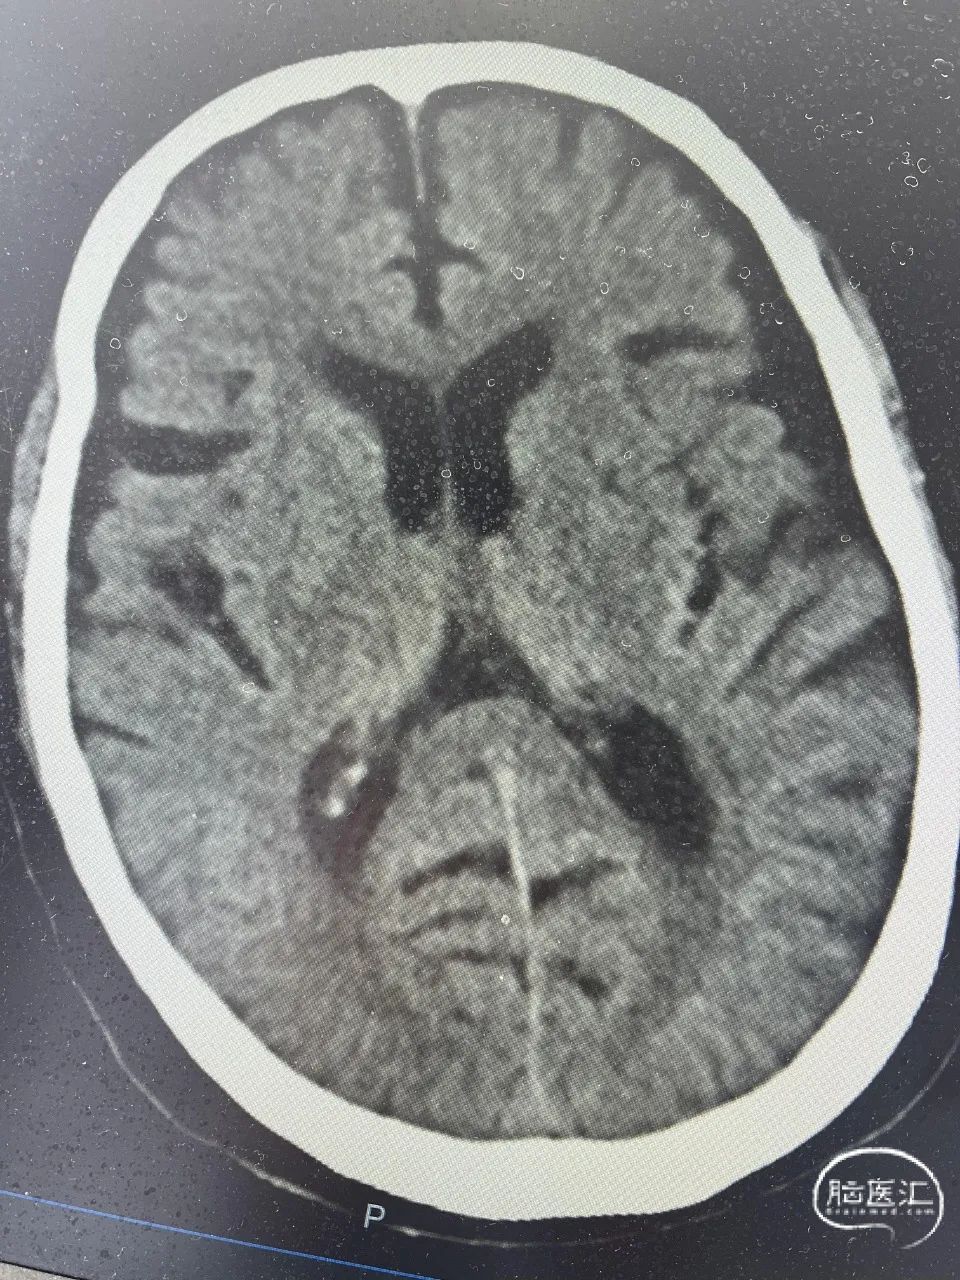

入院时头颅CT:多发腔隙性脑梗死灶。

术后24小时复查头颅CT无出血。